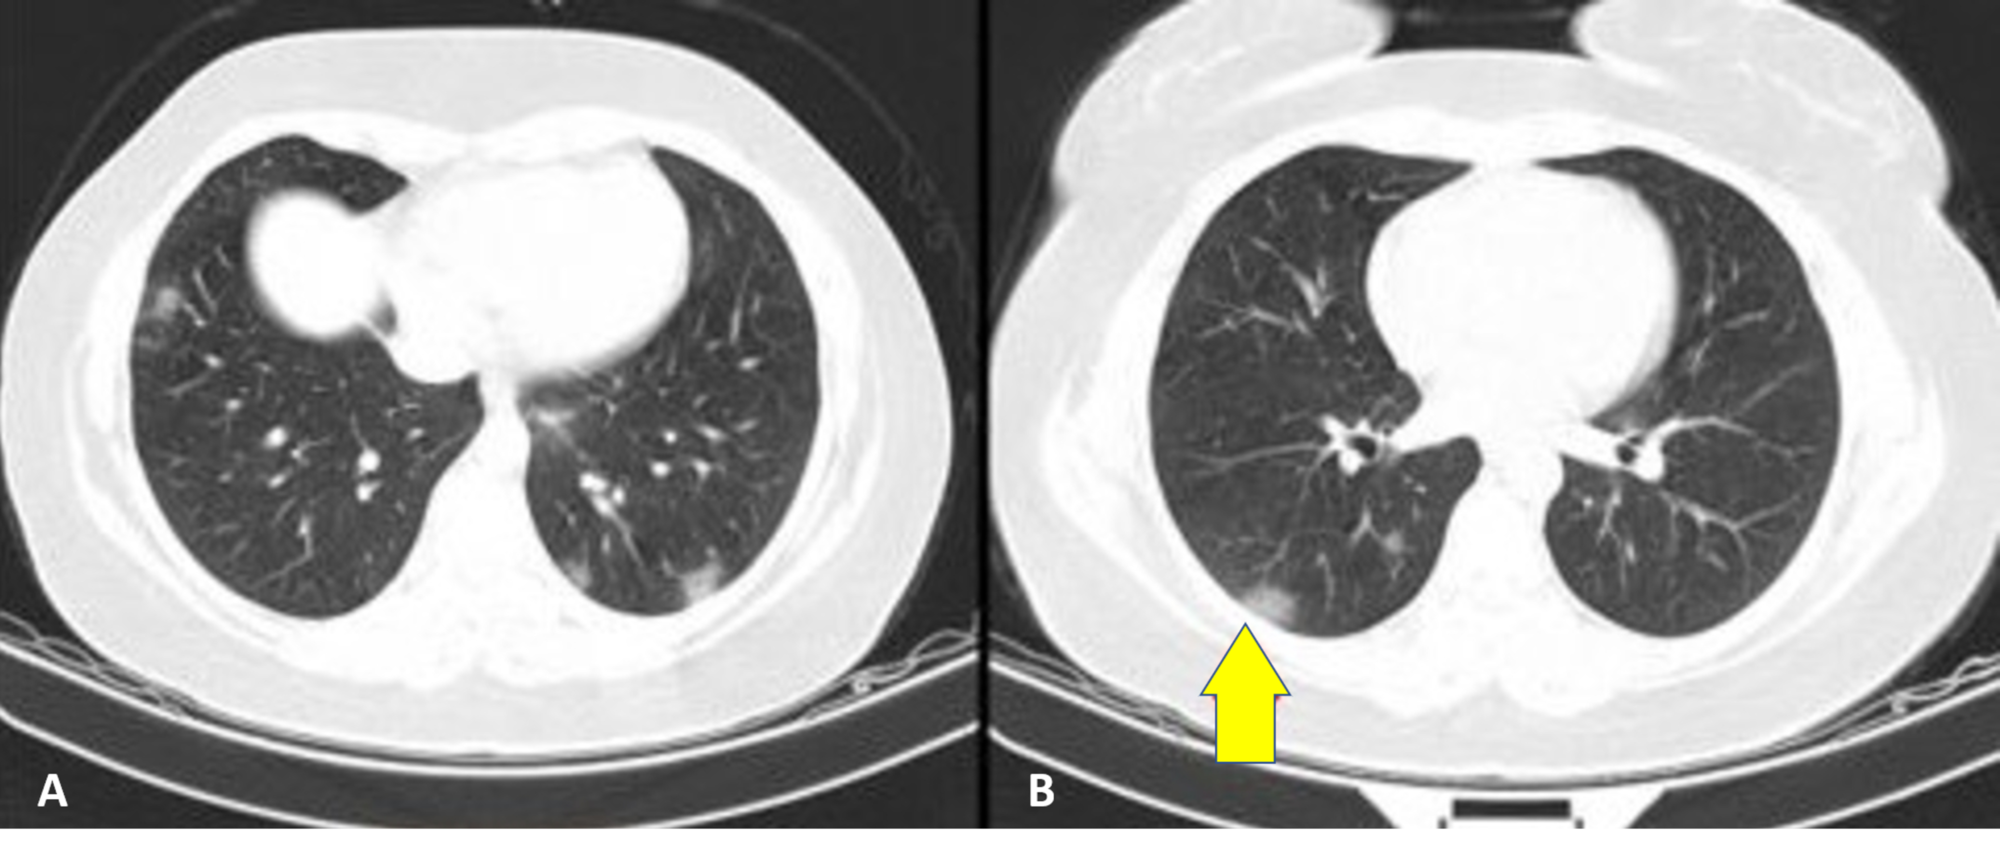

Different Computed Tomography Patterns Of Coronavirus Disease 2019 Covid 19 Between Survivors And Non Survivors Scientific Reports

www.nature.com